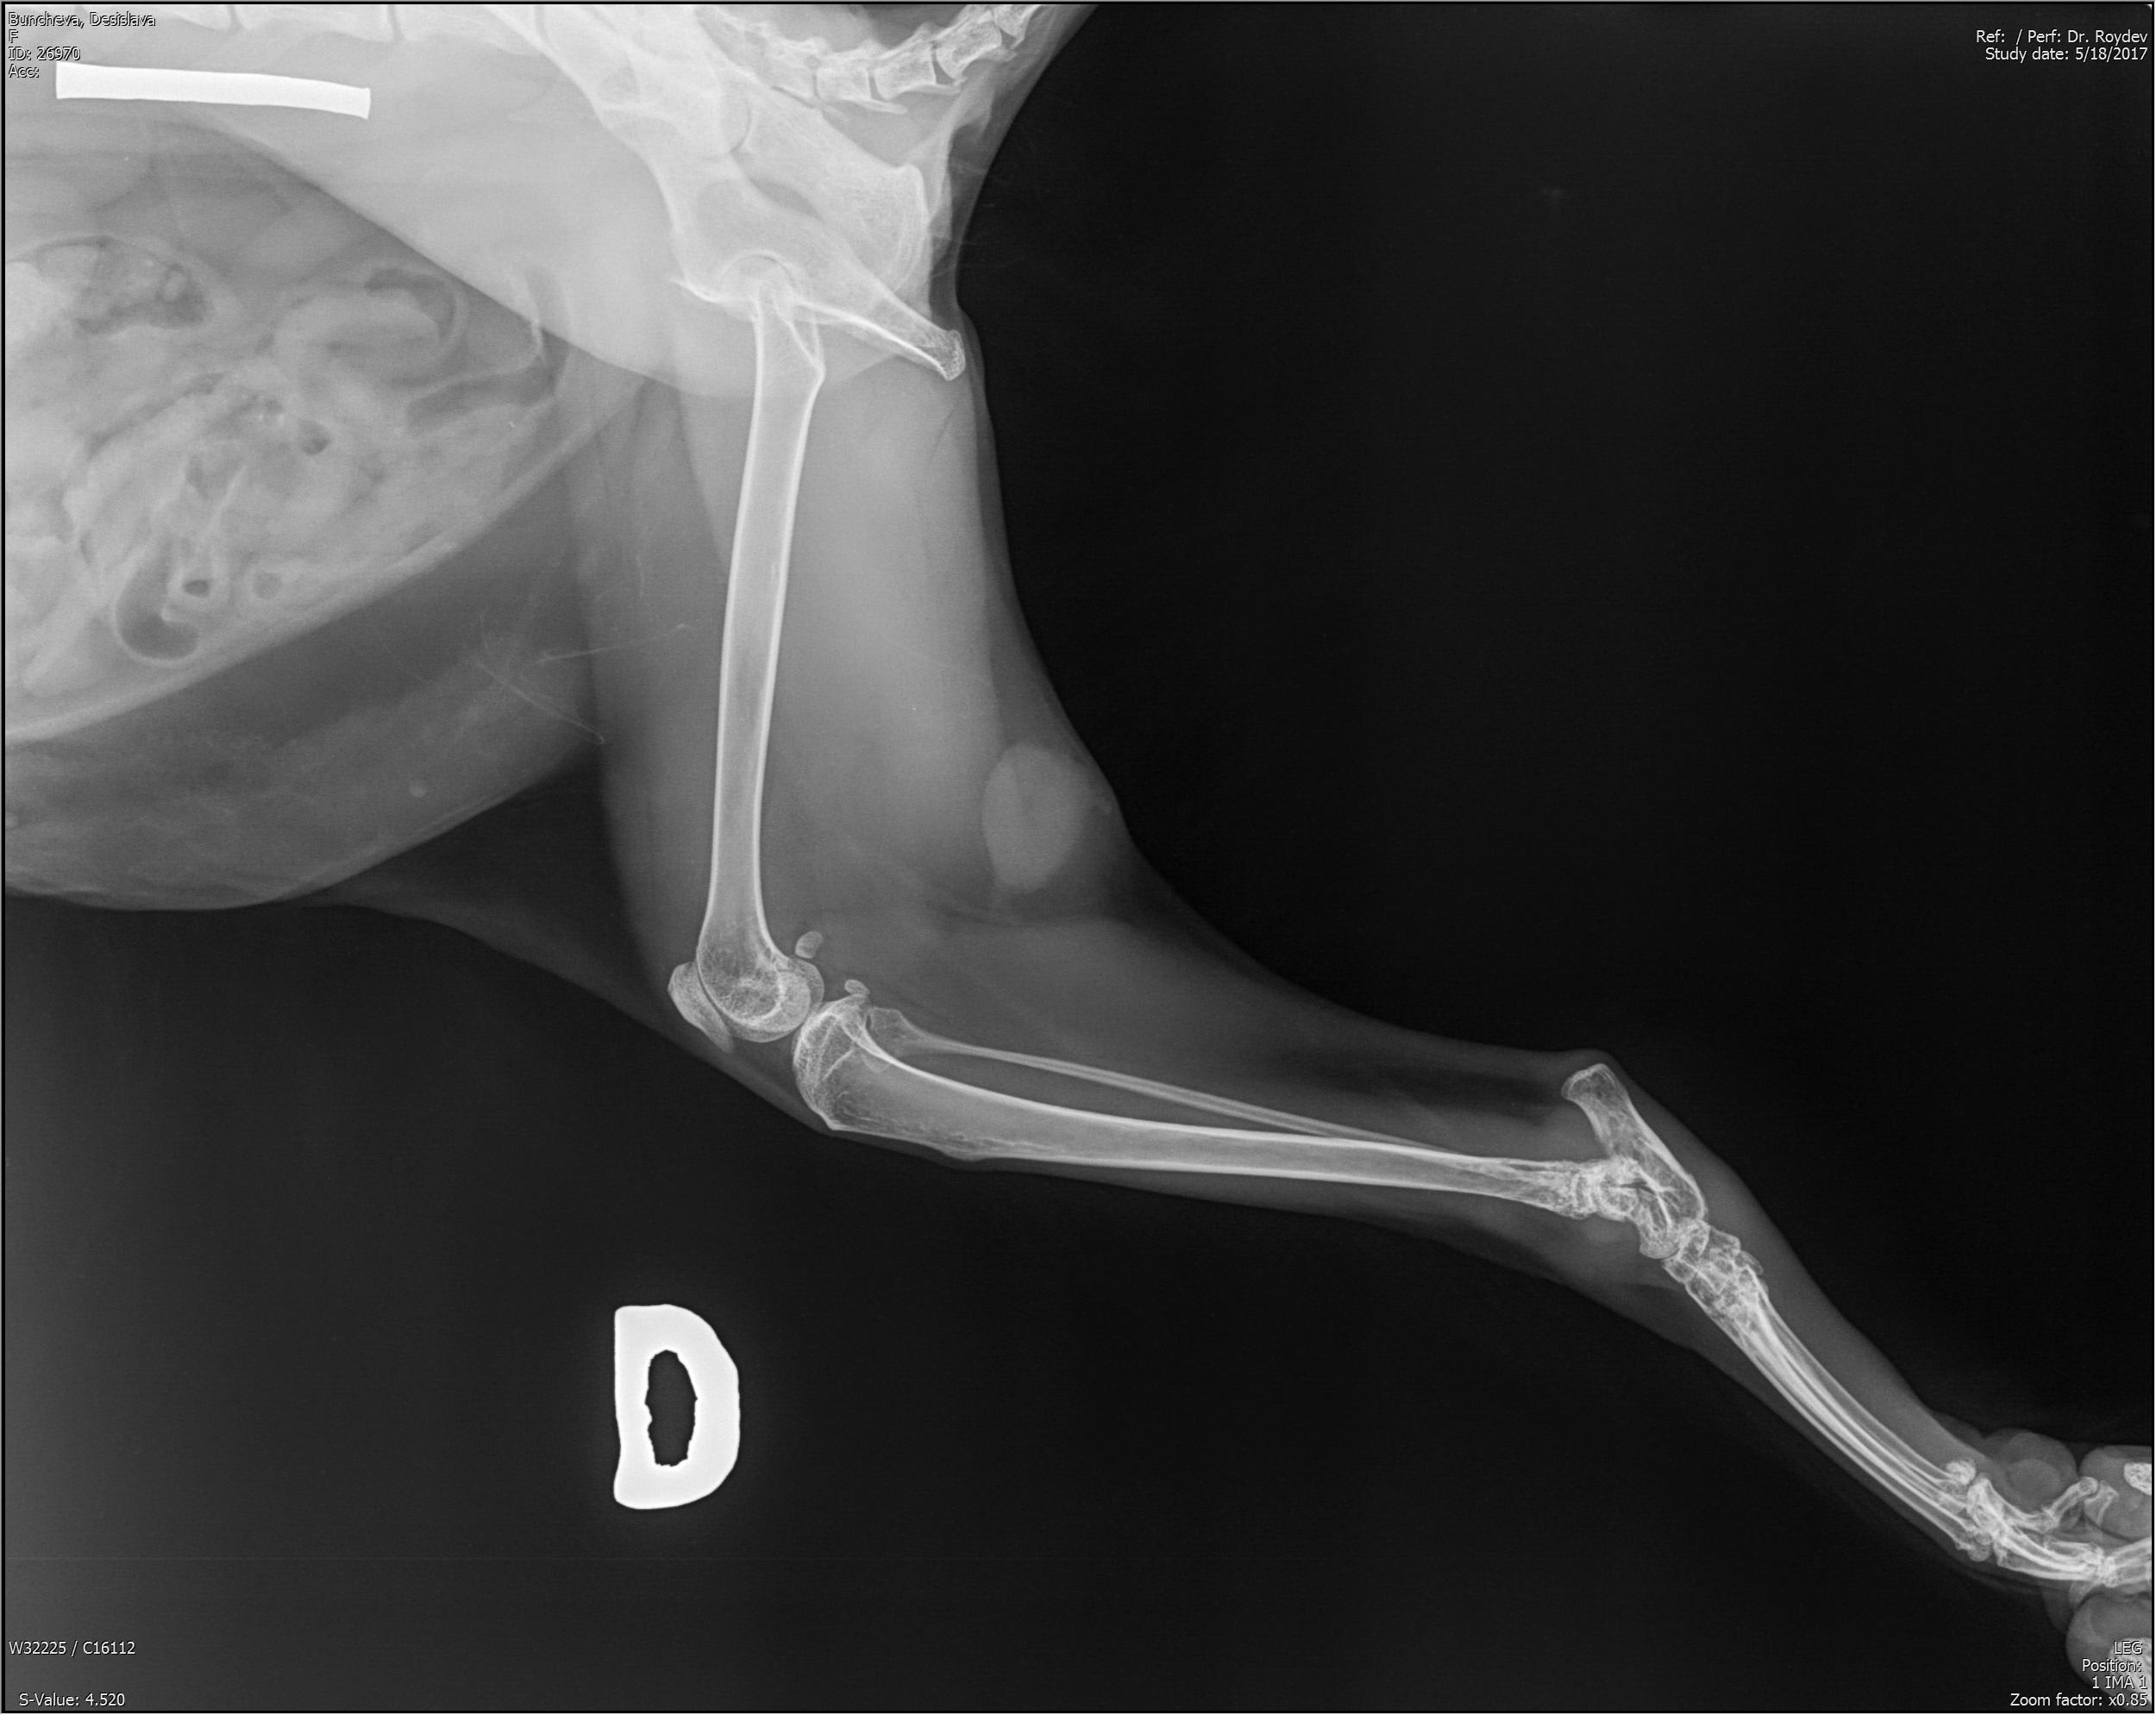

Hello, for about 6 months ago started to limb with her back right foot, when walking. We went to various doctors. For 1 month and a half she keeps her sick leg high in the air. Doctors think it is a tumor and we need to remove her leg. We don't have any bio tests done, only pictures. She is two years old. Can you tell from the pictures if it is a tumor and if so, are there alternatives?

It does look very suspicious for a tumour, a biopsy could be performed to confirm what is the underlying nature prior to amputation, referral to a veterinary university or specialist oncologist would ensure all options are fully explored for Audrey